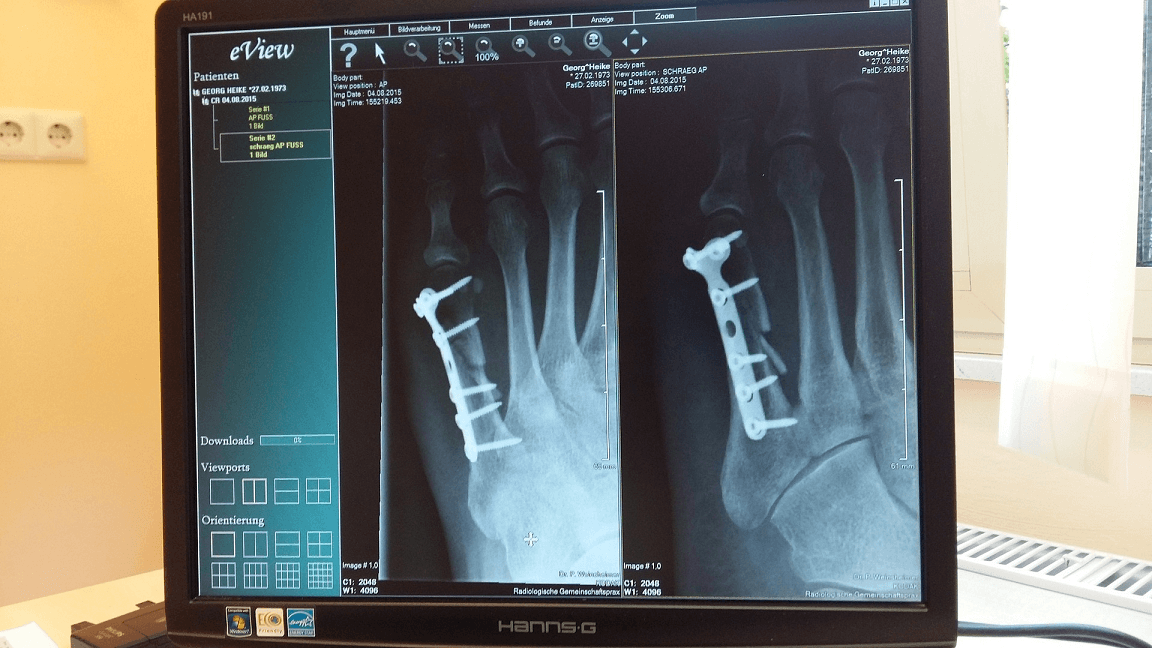

응급실 의료진들도 생업을 응급실에서 유지하고 있을 뿐이지 이런 사정은 마찬가지가 아닐까 싶습니다. 응급실에 근무 중인 한 응급구조사가 근무를 마치고 병원 식구들과 축구를 하다 넘어졌습니다. 그런데 땅을 짚고 넘어진 뒤 손에 통증이 지속되어 X-ray를 찍어 봤더니, 손목과 팔꿈치 두 군데에 골절이 확인되었습니다.

손목만 골절되었다면 짧은 부목을 대고 주위 도움 받아 가며 여차저차 일을 해 나갈 수 있을 겁니다. 하지만 팔꿈치까지 골절이 되었으니 아무리 응급실에서 그 같은 환자들을 많이 치료해봤다 한들 뭐 별 수 있겠습니까? 다른 환자분들이 그랬던 것처럼 그 친구도 팔 전체를 칭칭 감고 당분간 일을 하지 못하게 되었죠.